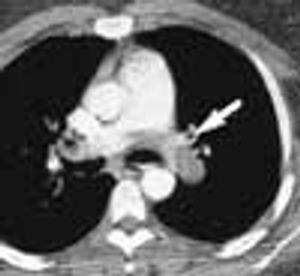

For 2 months, a 31-year-old woman had had dyspnea and dull, continuous retrosternal pain. She was admitted to the hospital, and a helical CT scan of the thorax identified a saddle pulmonary embolism. An ultrasonogram revealed deep venous thrombosis (DVT) in the left leg. Intravenous heparin was given; the patient was discharged, and warfarin was prescribed.

For 2 months, a 31-year-old woman had had dyspnea anddull, continuous retrosternal pain. She was admitted to thehospital, and a helical CT scan of the thorax identified asaddle pulmonary embolism. An ultrasonogram revealeddeep venous thrombosis (DVT) in the left leg. Intravenousheparin was given; the patient was discharged,and warfarin was prescribed.